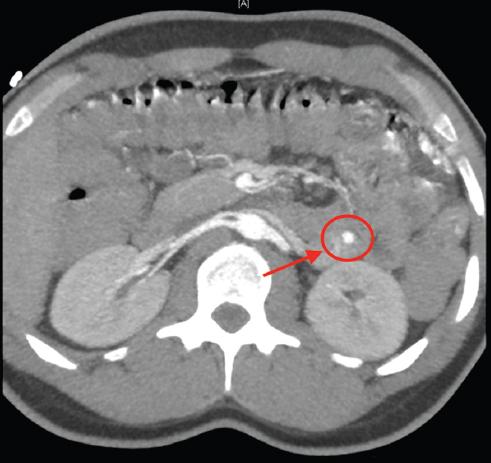

Ante la persistencia de las rectorragias abundantes que comprometían la estabilidad hemodinámica del paciente (120 latidos por minuto, 80/40 mmHg) y que requirieron la transfusión de 11 concentrados de hematíes, se realizó una angiografía por tomografía computarizada (Figs. 1 y 2), que mostró signos de sangrado activo en una lesión tumoral en el yeyuno medio. Se realizó embolización de la arteria dependiente de la arteria yeyunal por parte de radiología intervencionista (Fig. 3), inicialmente con éxito, y el paciente pasó a la unidad de reanimación posquirúrgica, sin precisar fármacos vasoactivos en ningún momento.

Figura 1 Opacificación focal nodular de contraste en la fase arterial de 6.5 mm a nivel mural endoluminal de un asa de yeyuno proximal.